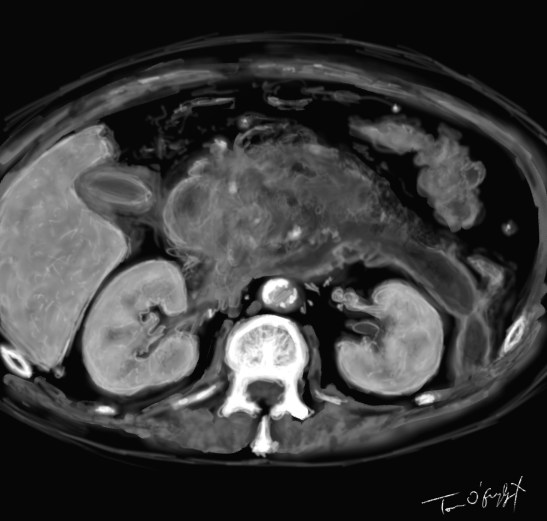

scanner de pancréatite aiguë nécrosante stade E avec importante réaction oedémateuse et coulée de nécrose

Publié le 3 décembre 2015 à 1463 × 1395 dans Pancréatite aiguë